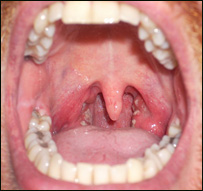

| | | که چېرې دخولې او غاښونوپاکوالي ته پاملرنه ونشي، تانسلونه مکروبي کيږي. |

تانسلونه (هډي)، چې عام وګړي يې په ستوني کې اضافي غوښې بولي، په بدن کې دمکروب پروړاندې دفاعي دنده پرمخ بيايي، چې له دې امله ډېری وخت پخپله مکروبي کيږي. روغتيايي کارپوهان دتانسلونومکروبي کېدل نه يواځې ساري بلکې يوه ارثي ناروغي هم ګڼي. دستوني، غوږ او پزي متخصص ډاکتر صديق الله رښتين دنورو ترڅنګ د خولې او غاښونو پاکوالي ته نه پاملرنه هم ددې ناروغۍ لامل وګاڼه. هغه کسان، چې تانسلونه يې مکروبي شوي وي، دسختې تبې او ځان دردۍ ترڅنګ يې د ستوني لاندنۍ برخه کې پړسوب هم ليدل کيږي.  | | | دتانسلونومکروبي کېدل نه يواځې ساري بلکې يوه ارثي ناروغي هم ګڼي. |